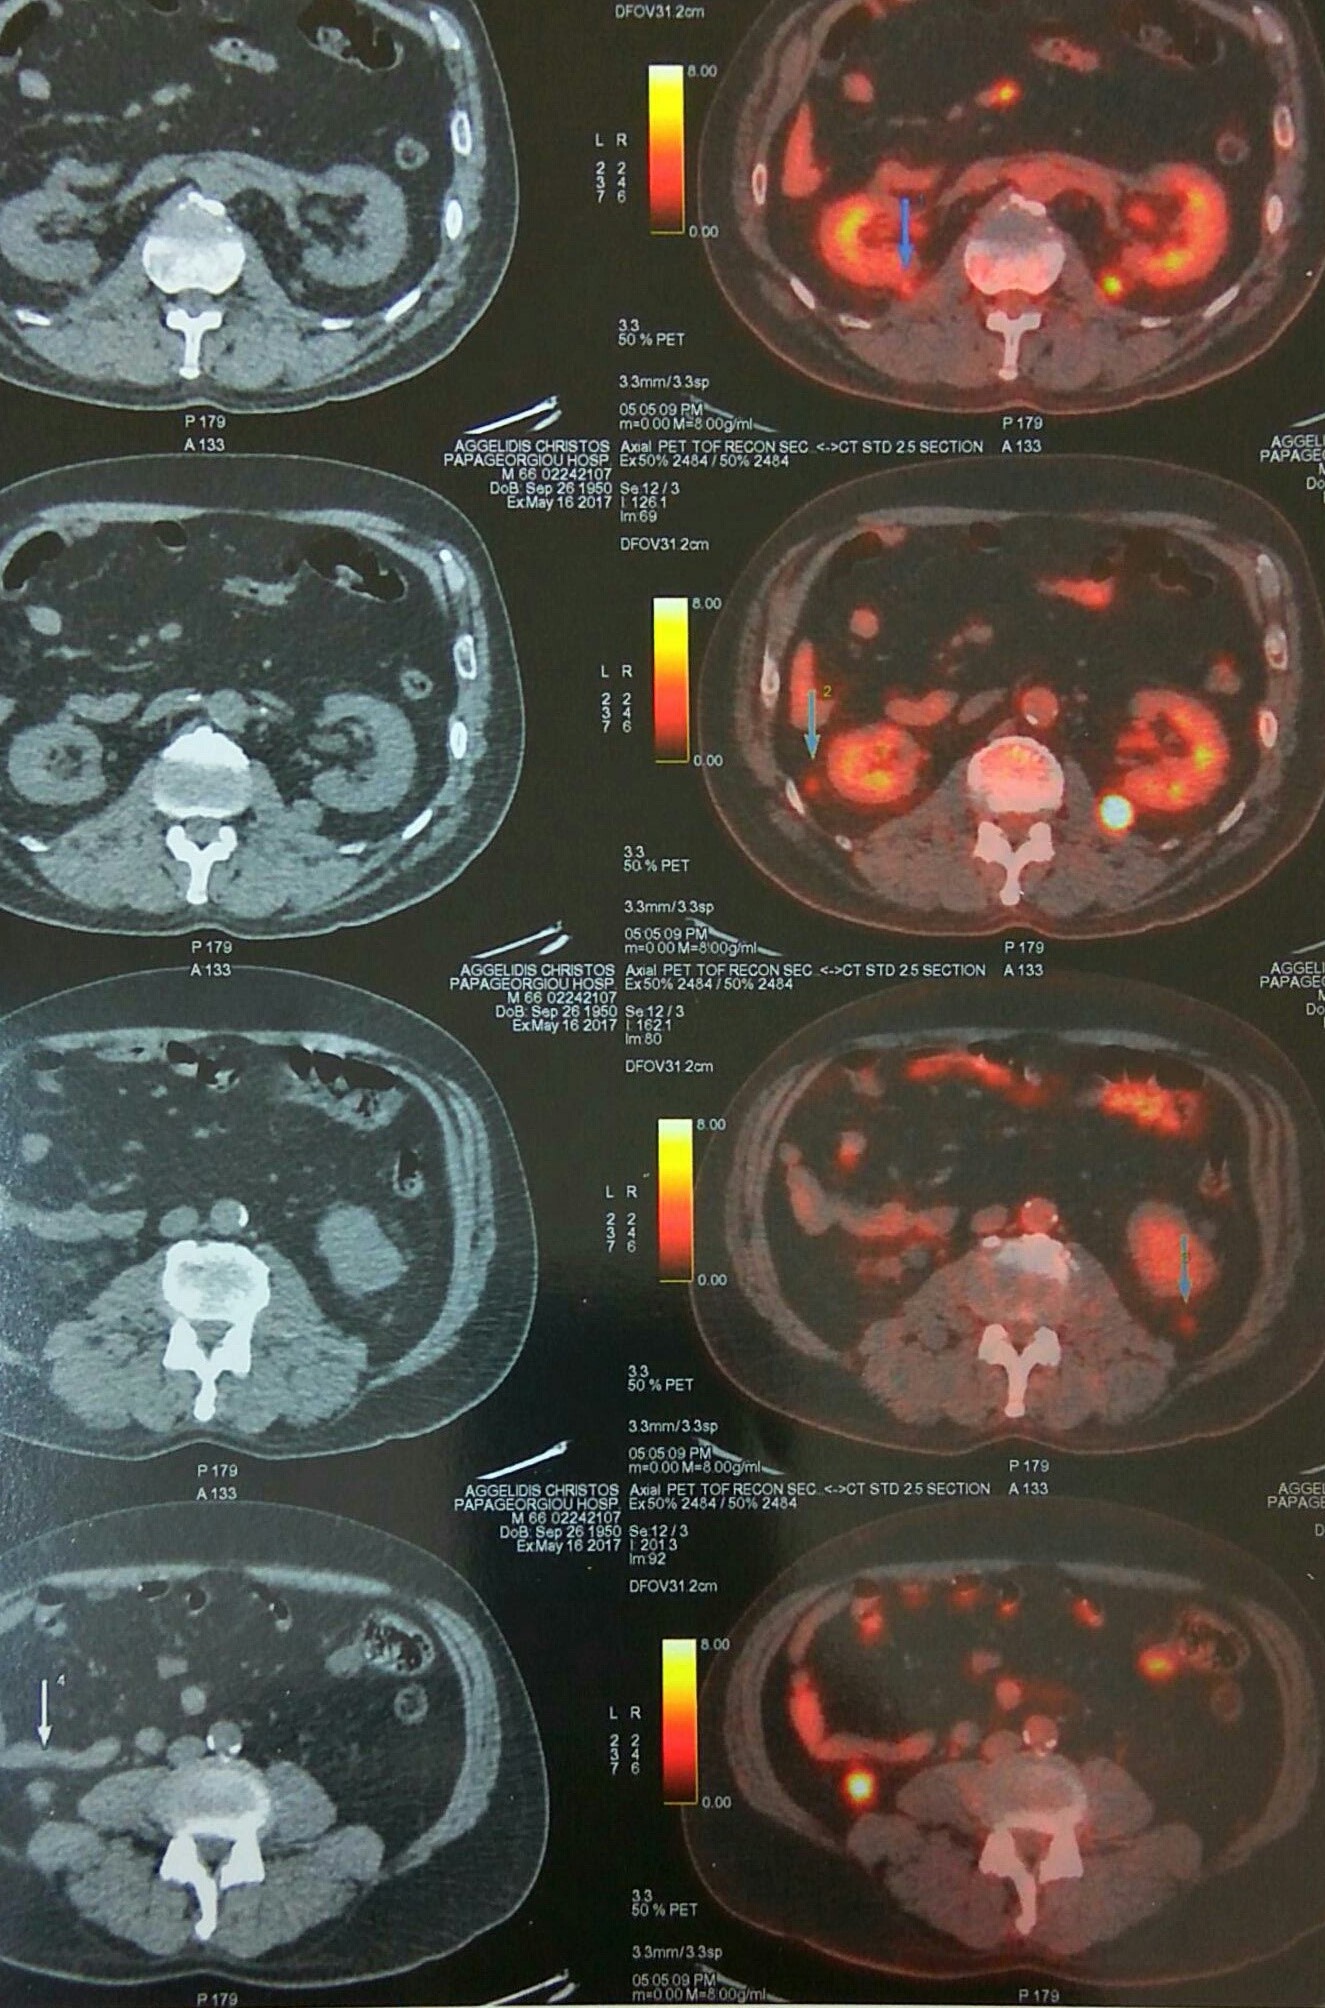

Αξονική τομογραφία κοιλίας. Φεβρουάριος 2017. Εμφανίζεται η υποτροπή του οπισθοπεριτοναϊκού αγγειοσαρκώματος (κόκκινα βέλη)